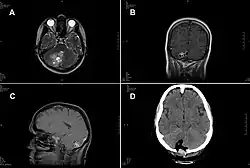

A case of intracranial T. crassiceps tapeworm cysticercosis with severe involvement of the cerebellum is described. A 51-year-old German woman was hospitalized because of progressive headache, nausea, and vomiting. The signs and symptoms had started two weeks before, and intensity had been increasing ever since. At the time of admission, the patient showed cerebellar ataxia but no further neurologic deficits. She did not have fever or other symptoms. She had no known chronic preconditions or recent hospital stays and had never taken immunosuppressant drugs. She had no family history of neurologic symptoms or malignant diseases. Combined surgical removal of the larvae and treatment with albendazole and praziquantel led to a complete cure in this nonimmunocompromised patient. The organism was unequivocally identified by molecular methods, thus avoiding a misdiagnosis of Taenia solium tapeworm cysticercosis.[5]